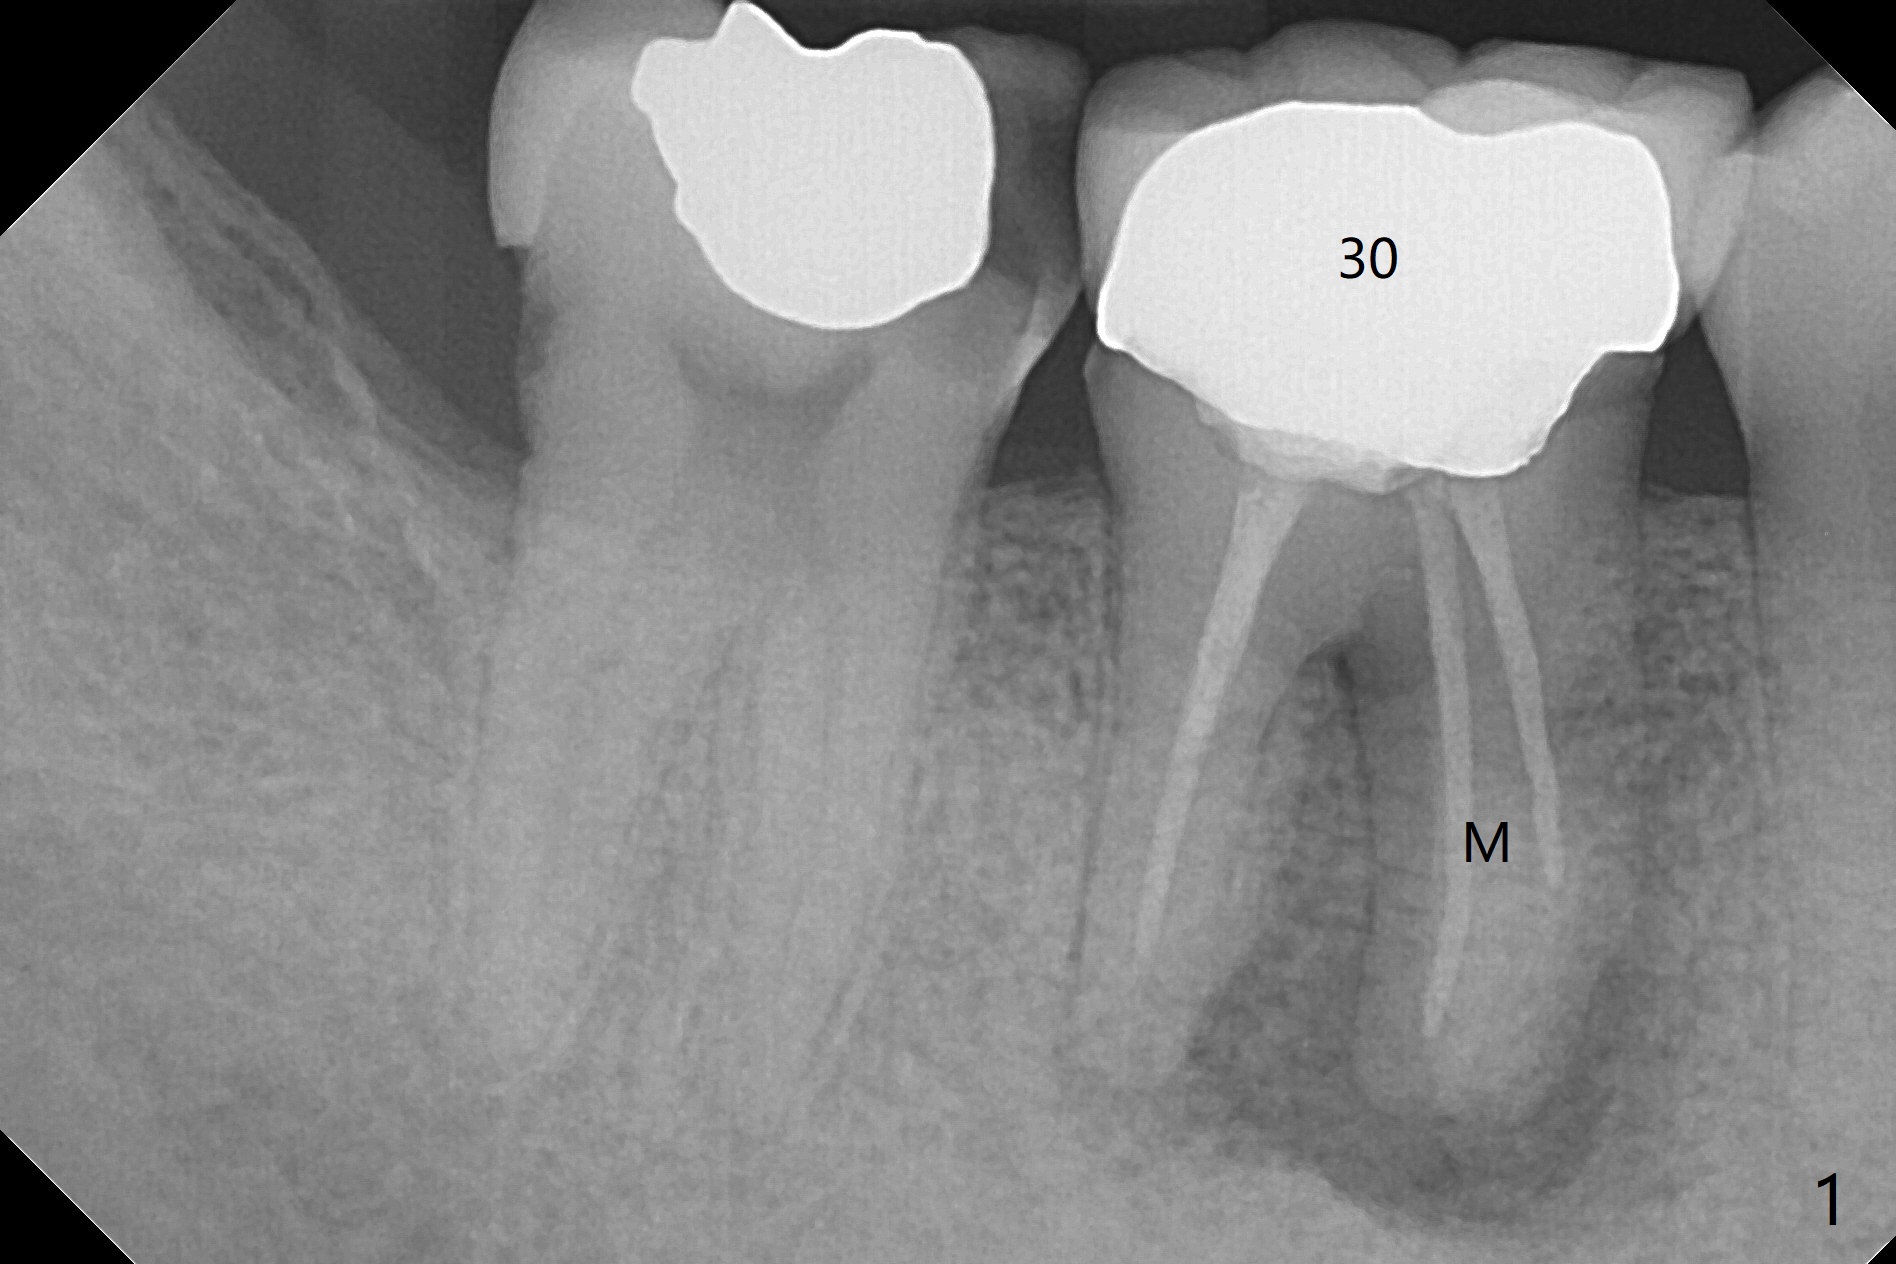

A 47-year-old man has poor dentition. The tooth #31 needs RCT, while #30 has severe PARL, especially mesial (Fig.1 M). The buccal roots are exposed (Fig.2). Between the exposed roots is the septal gingiva, which will be saved for buccal soft tissue repair (Fig.3 *). The septal gingiva will keep in place (not to be transferred) so that the recession will disappear by epithelial regrowth from the nearby gingiva (Fig.3' arrows) over the bone graft and PRF. The provisional should be fabricated to cover the soft tissue defect (Fig.3'' yellow area). In fact the mesial root fractures (Fig.4 ^), as related to the severe bony defect. There seems to be enough lingual bone to hold a 4x13 mm implant (Fig.5 green). Sticky bone (Fig.6 red circles) and PRF (blue) are to be used to repair the hard and soft tissue defects following an immediate provisional (Fig.5,6 yellow outline). Extra layer of acrylic (Fig.6 orange) will be used to cover the PRF buccally. The base of the buccal plate is thick (Fig.6 *); mesial portion appears to be denser (Fig.7 black *) than the distal one (white *). Decortication will be done if hemorrhage is insufficient. Fig.8 is a coronal section of the socket (B: buccal). Extraction (Fig.9 black area) will most likely result in a knife edge ridge. Extraction with bone graft may not fare better, as it is easy to lose the graft considering missing buccal hard and soft tissues.